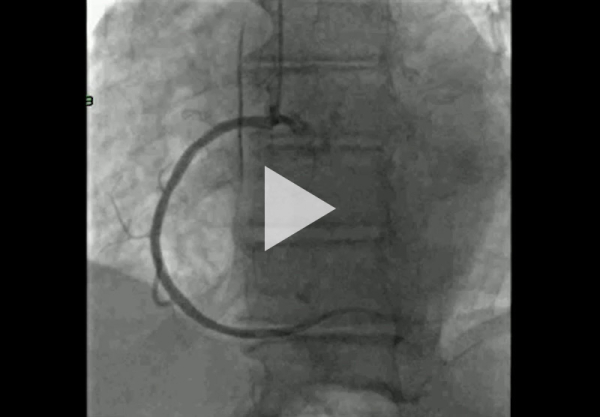

Nous optons ensuite pour une coronarographie devant sa symptomatologie de dyspnée, ses facteurs de risque cardiovasculaires et la présence d’hypokinésie du VG, en faveur d’une lésion monotronculaire avec sténose significative de la première marginale, laissée au traitement médical.

Boucles de coronarographie jointes :

- Réseau coronaire gauche (Vidéo 6)

- Réseau coronaire droit (Vidéo 7)

Vidéo 6 - Réseau coronaire gauche

Vidéo 7 - Réseau coronaire droit